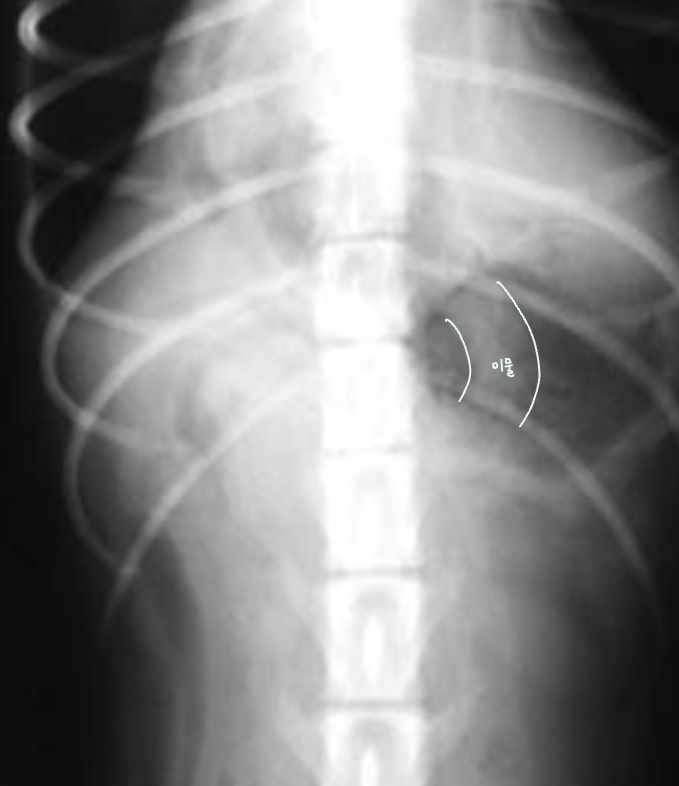

์ ๋ฆฝ์ ๋น๋

| Benign prostatic hyperplasia (BPH) |

|---|

| (๋ฐฐ์ฐ์ง ์์์ง๋ง ์กฑ๋ณด์ ๋ฑ์ฅํ๋ ๋ณ๋ช

.) ์ ๋ฆฝ์ ๋น๋์ ์ํด - ์๋๊ฐ ์๋ฐ๋์ด ๋ฐฉ๊ด์ cranial margin์ด ํฝ๋๋จ. - ์ ๋ฆฝ์ ๊ณผ ๋ฐฉ๊ด ์ฌ์ด์ ์ง๋ฐฉ์ ๊ฒฝ๊ณ๊ฐ ์๊ฒจ ์ผ๊ฐํ ๋ชจ์์ radiolucentํ ์์์ด ๋ํ๋จ. ![]() |